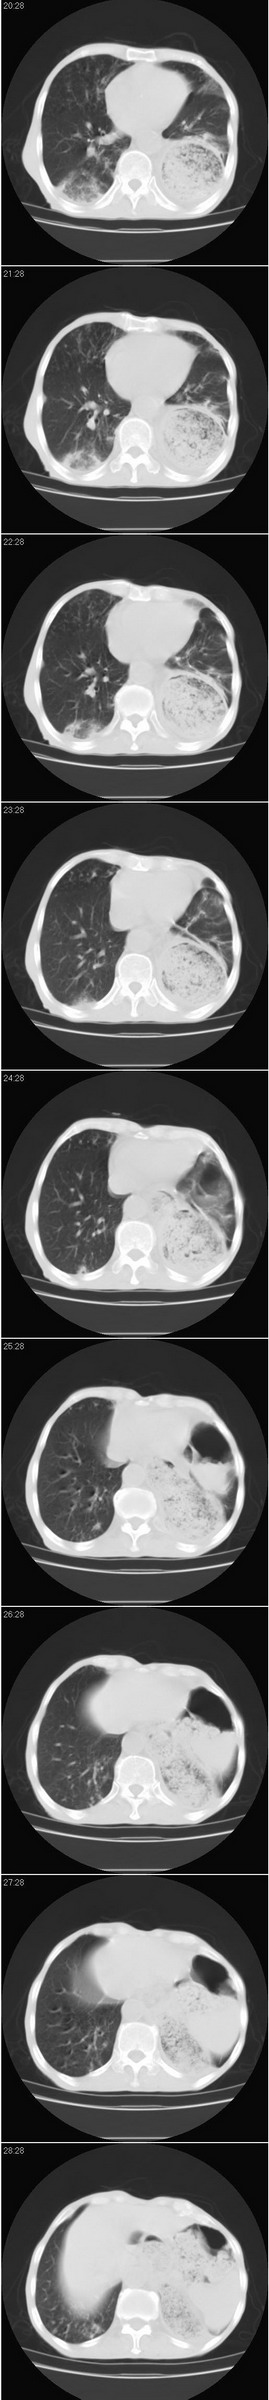

以下是引用dyqct在2007-8-18 14:40:00的发言:[br]考虑:1、食道弓上吻合术后(左侧胸腔胃);[br] 2、右上继发型肺结核;[br] 3、慢性支气管炎合并全小叶型肺气肿、感染。

以下是引用andymaomao在2007-8-18 14:29:00的发言:[br][br]1.该患者应有食道ca手术史,胃位于左侧胸腔(后纵膈旁);[br]2.双肺继发性肺tb?!不排除部分病灶改变为转移灶;[br]3.纵隔气管旁可见肿大淋巴结;[br]4.右下侧后胸壁轻度增厚、粘连。[br]5.另左肺部分肺组织含气不良(受压!?)。[br][br]